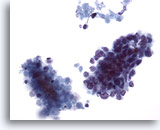

画像 3

肝FNA – 良性肝細胞

核はわずかに大小不同であり、反応性変化を来した肝細胞に典型的な低N/C比を示します。微小な細胞質空胞および細胞質内色素がみられます。

60倍

画像 3

肝FNA – 良性肝細胞

核はわずかに大小不同であり、反応性変化を来した肝細胞に典型的な低N/C比を示します。微小な細胞質空胞および細胞質内色素がみられます。

60倍